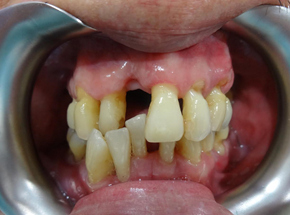

This is how his dentition and gum condition when he first saw me. Scaling was done prior to photo taking. His oral hygiene was compromised, and one of the upper front incisor is wobbly, with gum boil. Thorough examination for his teeth and gum was done. He wanted gum therapy and hope to save his other teeth, if possible. He also understood that gum therapy is a tedious procedure and needs his co-operation in term of good ora hygiene home care routine.

It is a always a standard procedure to take X-ray and periodontal charting (to measure the ‘cuff’ of gum around each tooth to see if there is any sign that periodontal disease has started and the severity) as a baseline record. X-ray is needed to see the amount of bone that has been lost. We did the same thing for this gentleman, severe bone loss was noticed at the lower front teeth region but he refused to extract them. The lower front teeth are loose but did not disturb his chewing, and most importantly, there was no active infection. After discussion, we decided to keep them and will only remove them in future if worsening. Those were considered hopeless teeth.